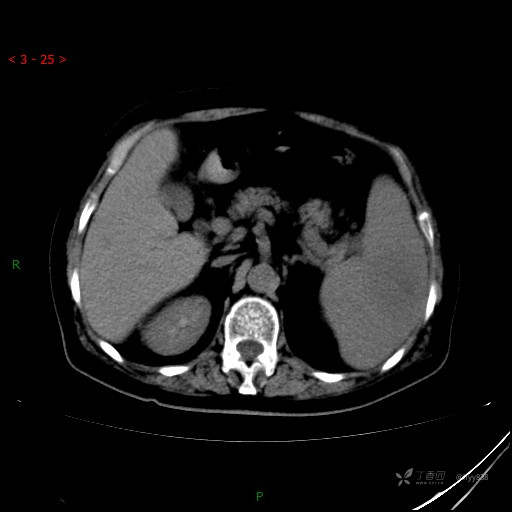

上腹部CT平扫